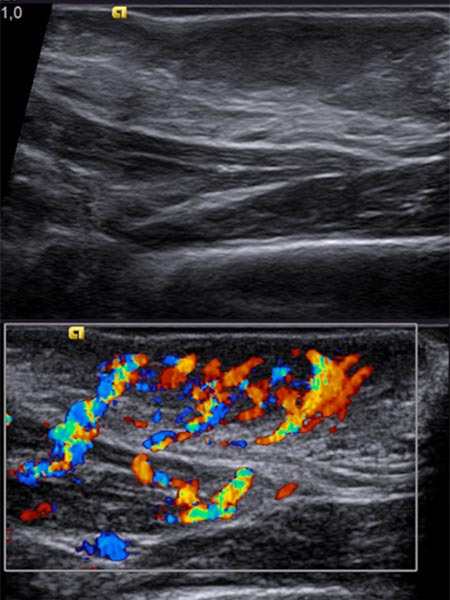

Nachdem am Ende des 3. Lebensjahres immer noch keine Rückbildungstendenz des Tumors sichtbar war, wurde nach einer Biopsie eine Embolisation zur Induktion einer Involution durchgeführt. Die Digitale Subtraktionsangiographie (DSA) zeigt einen Mikrokatheter superselektiv in einem Tumorgefäß. Der Tumor ist stark perfundiert und lobuliert, sehr früher venöser Abstrom, typisch für ein NICH.

Partikelembolisation mit sphärischen Partikeln der Größe 250 Mikrometer über den superselektiv in den Tumor eingeführten Mikrokatheter.

Weitere Tumorgefäße mit blush-artigem, diffusem Enhancement, typisch für Gefäßtumor/NICH. All diese Gefäße müssen selektiv embolisiert werden um eine Involution zu induzieren.

Weitere selektive Partikelembolisation. Die mit Kontrastmittel gemischten Embolisationspartikel verbleiben in den Tumorgefäßen.